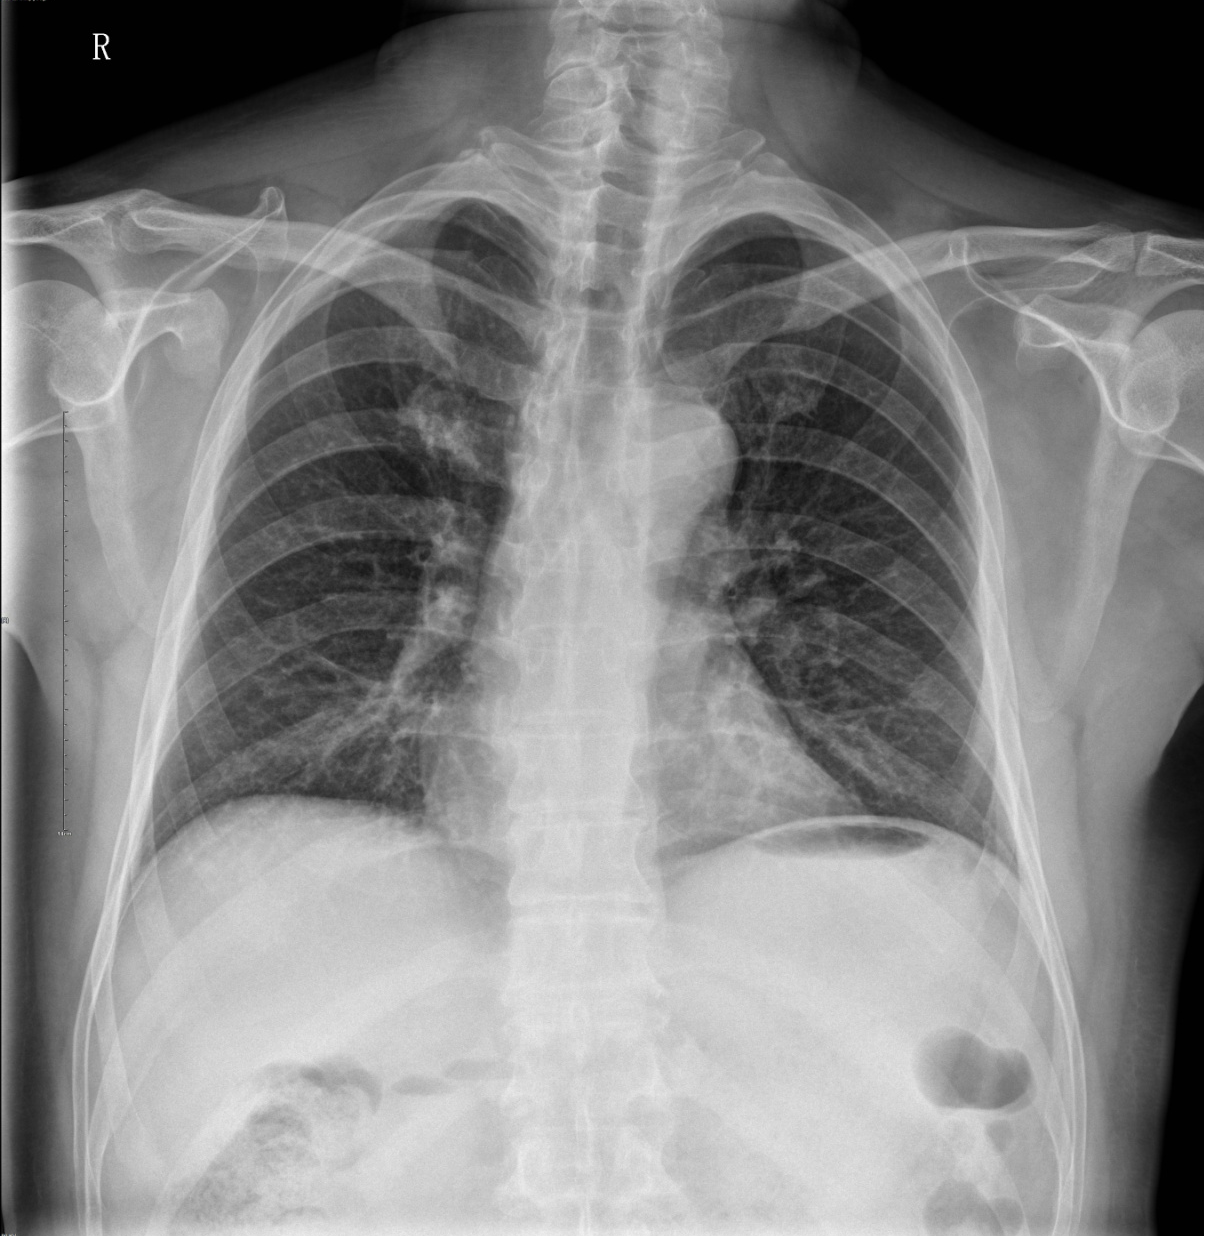

X线检查几乎没有人不知道,但是我们常常能在日常生活中听到做X线检查危害很大,那么到底做X线检查对人体有哪些危害呢?

我们每时每刻都在受各种辐射,辐射按照来源可分为天然辐射和人工辐射。天然辐射包括宇宙射线、地壳陆地辐射、室内外环境中的氯等,它遍布于我们的整个生活环境中,空气、食物和饮料中都存在着天然放射性。人工辐射主要来源于医疗照射(也就是我们做的X线、CT)、矿物开采、核动力生产、射线装置、核爆炸及核试验等,其中医疗照射是最大的人工辐射源。

以拍X光片来说,现在你每拍一张“吃进”的射线量约0.02毫西弗左右。这其实就相当于每天看电视或看电脑累及4到6个月“吃进”的射线量,对身体的影响微乎其微。

虽然X线检查对身体或多或少有危害,但只要检查时机、次数适宜,应该是无害的。从诊断疾病与X线损伤两者比较来说,无疑前者更为重要。当然,我们要注意射线具有累积效应,过于频繁、长期的X射线检查应尽量避免。